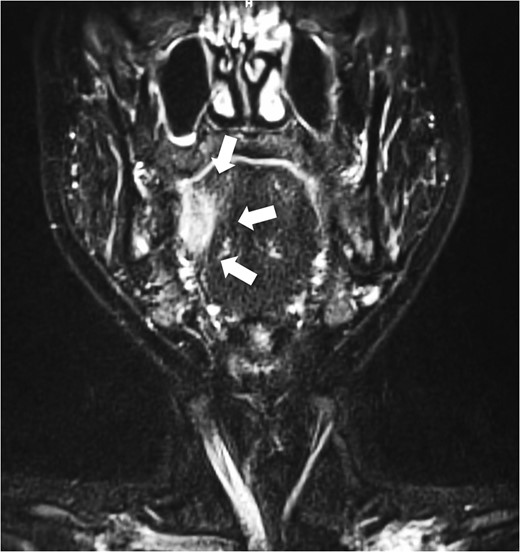

A 33-year-old woman with a squamous cell carcinoma of the right lateral border of the tongue, who was 25 weeks pregnant (gravida 5 para 4). The lesion measured 23 × 8 mm2 (Fig. 1). Infiltration into tongue muscle was observed in MRI image (Fig. 2). The patient was staged as T2, N0 and M0. Discussion between surgical teams and obstetricians were held and agreed to continue her pregnancy while managing the tumour. Complete resection of the tumour was affirmed to be essential in controlling the cancer.

Pre-operative coronal MRI. Invasion into tongue muscle was observed. White arrow indicates the tumour.